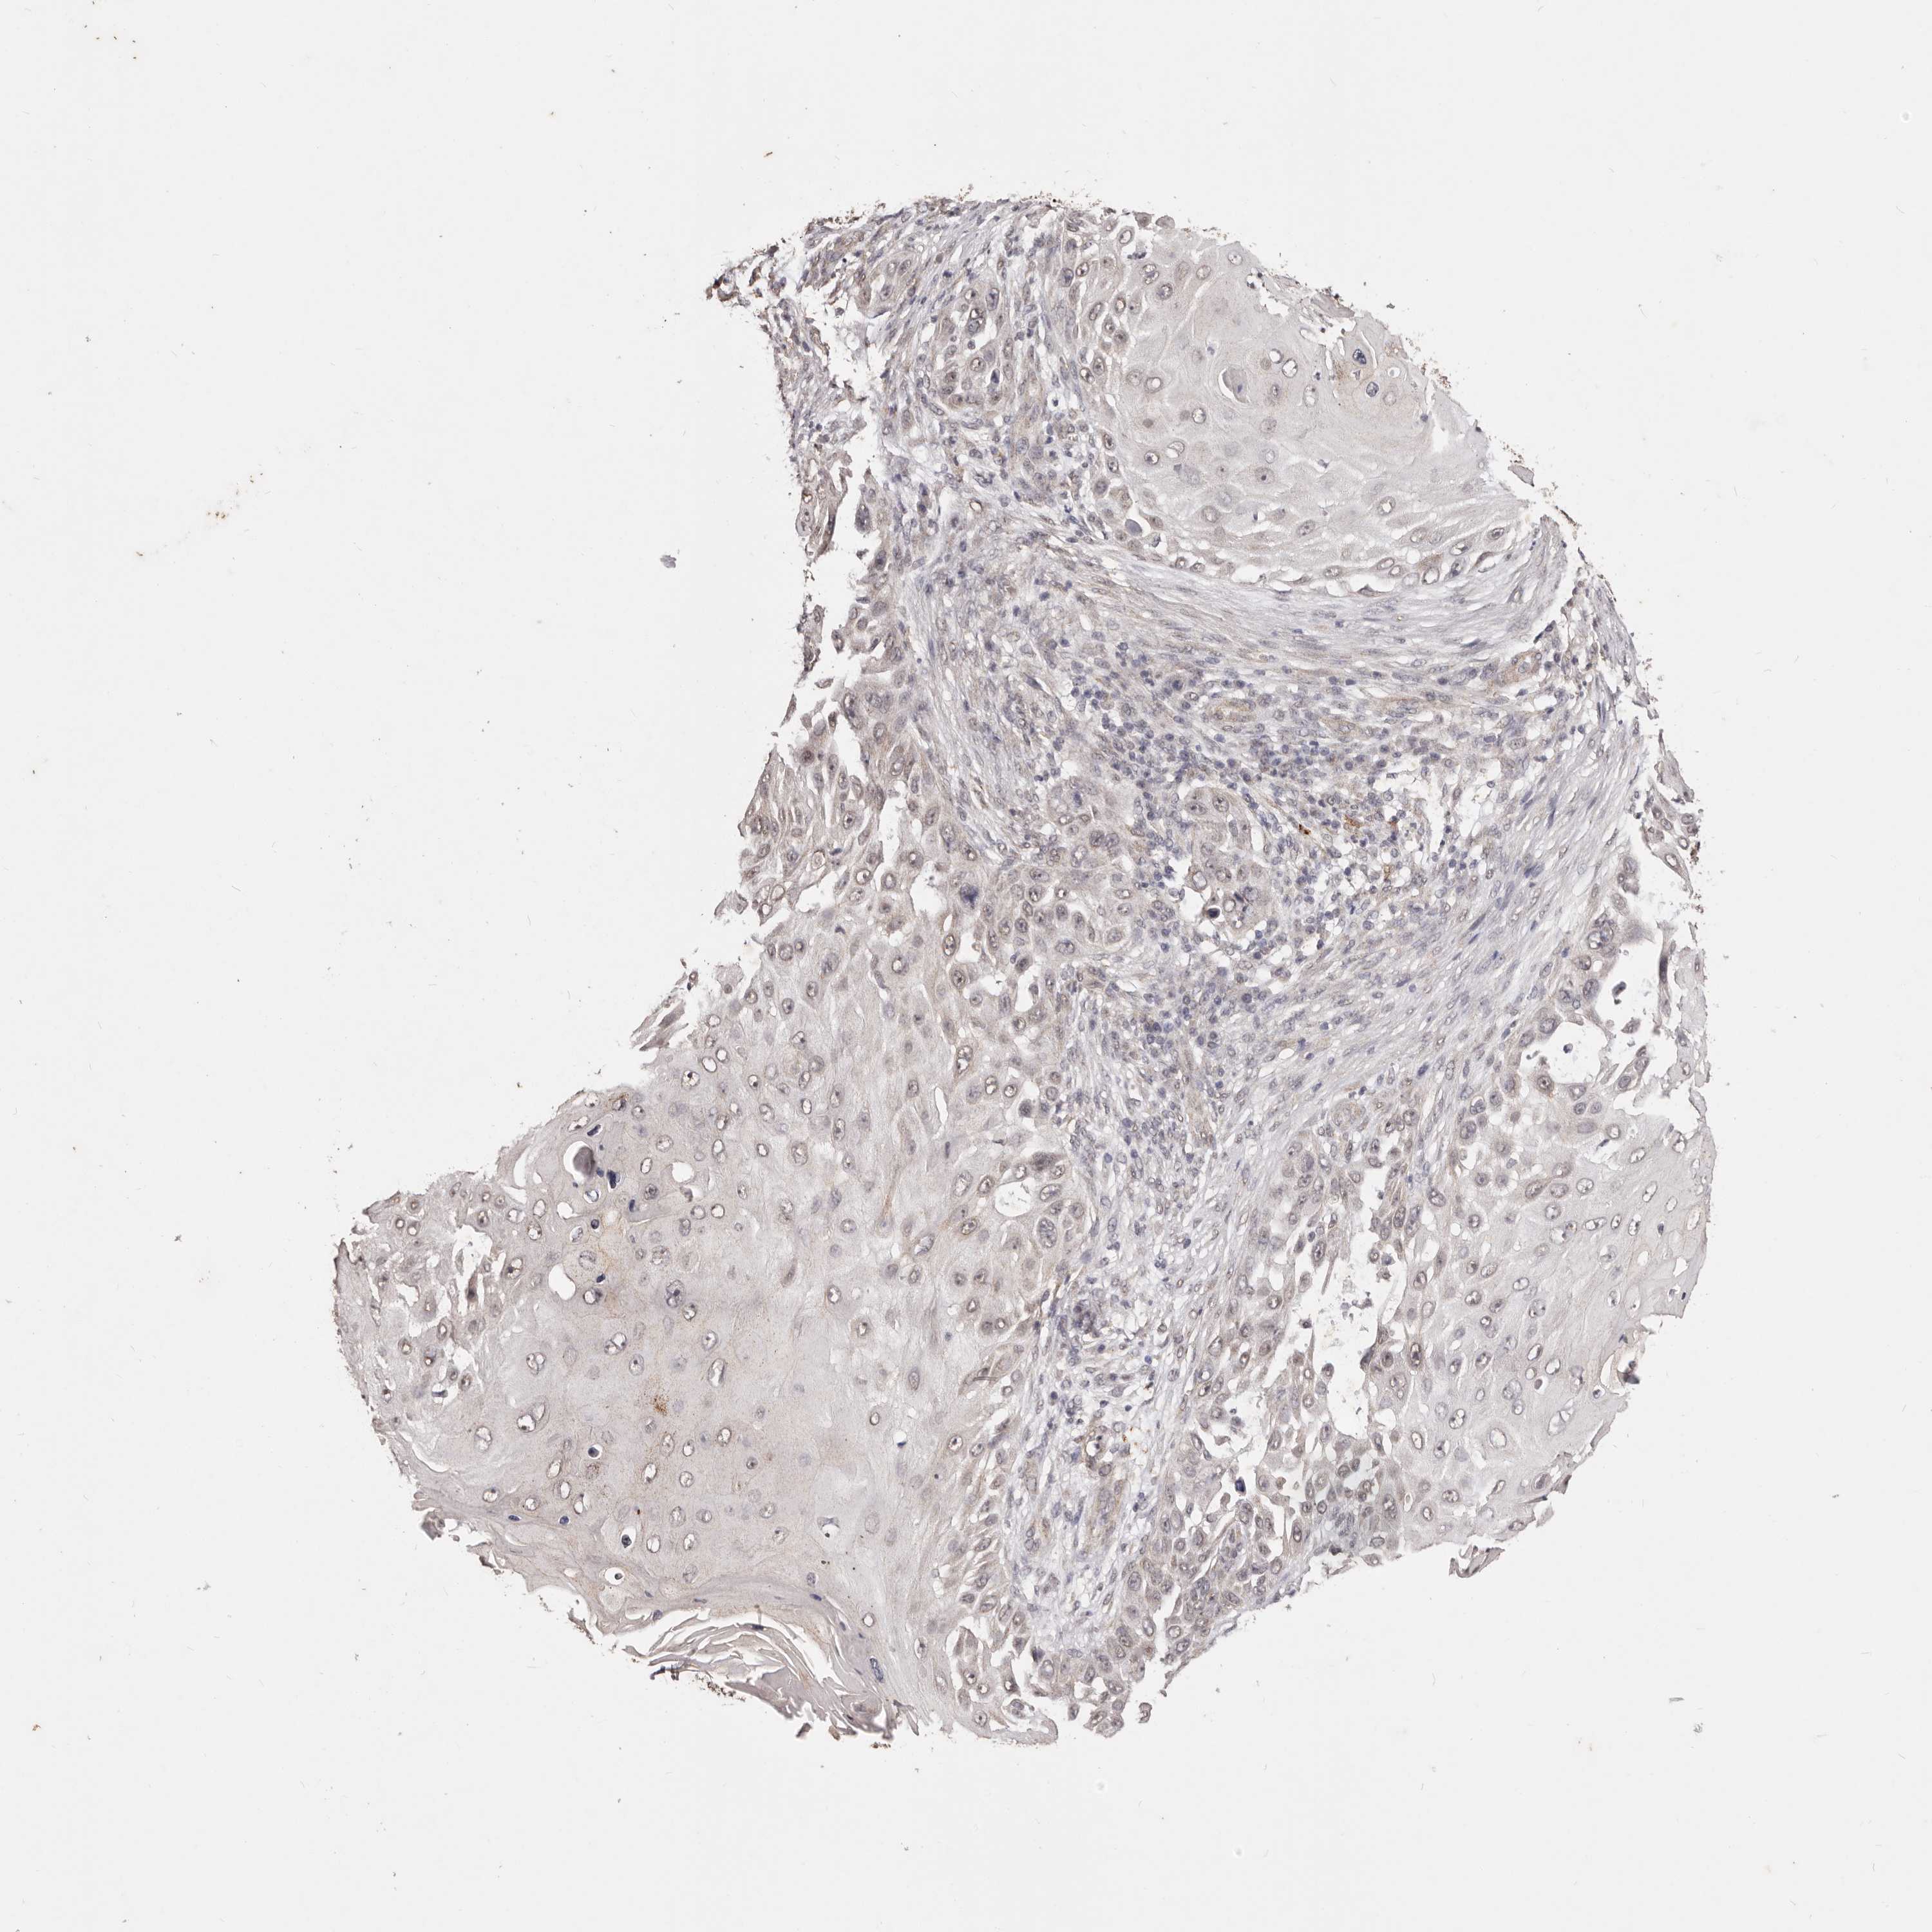

SKIN CANCER - Protein expressioni

A mouse-over function shows sample information and annotation data. Click on an image to view it in a full screen mode. Samples can be filtered based on level of antibody staining by selecting one or several of the following categories: high, medium, low and not detected. The assay and annotation is described here.

Antibody staining in the annotated cell types in the current human tissue is reported as not detected, low, medium, or high, based on conventional immunohistochemistry profiling in selected tissues. This score is based on the combination of the staining intensity and fraction of stained cells.

Each image is clickable and will lead to virtual microscopy that enables deeper exploration of all samples and also displays staining intensity scores, fraction scores and subcellular localization as well as patient and tissue information for each sample.

Antibody HPA001274

Antibody CAB025458

Staining

Squamous cell carcinoma, NOS

Basal cell carcinoma